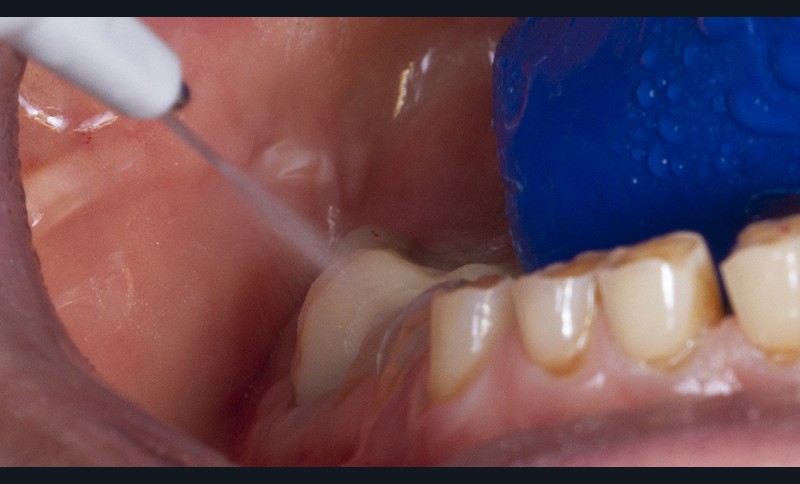

Un sablage à l’oxyde d’alumine est recommandé lorsque les usures sont marquées afin de préparer la surface de collage. Après rinçage, un mordançage à l’acide orthophosphorique est réalisé pendant 30 secondes sur l’émail et 15 secondes sur la dentine. Après un rinçage scrupuleux, un adhésif est étalé sur l’ensemble des surfaces mordancées, soufflé puis photopolymérisé (fig. 5).